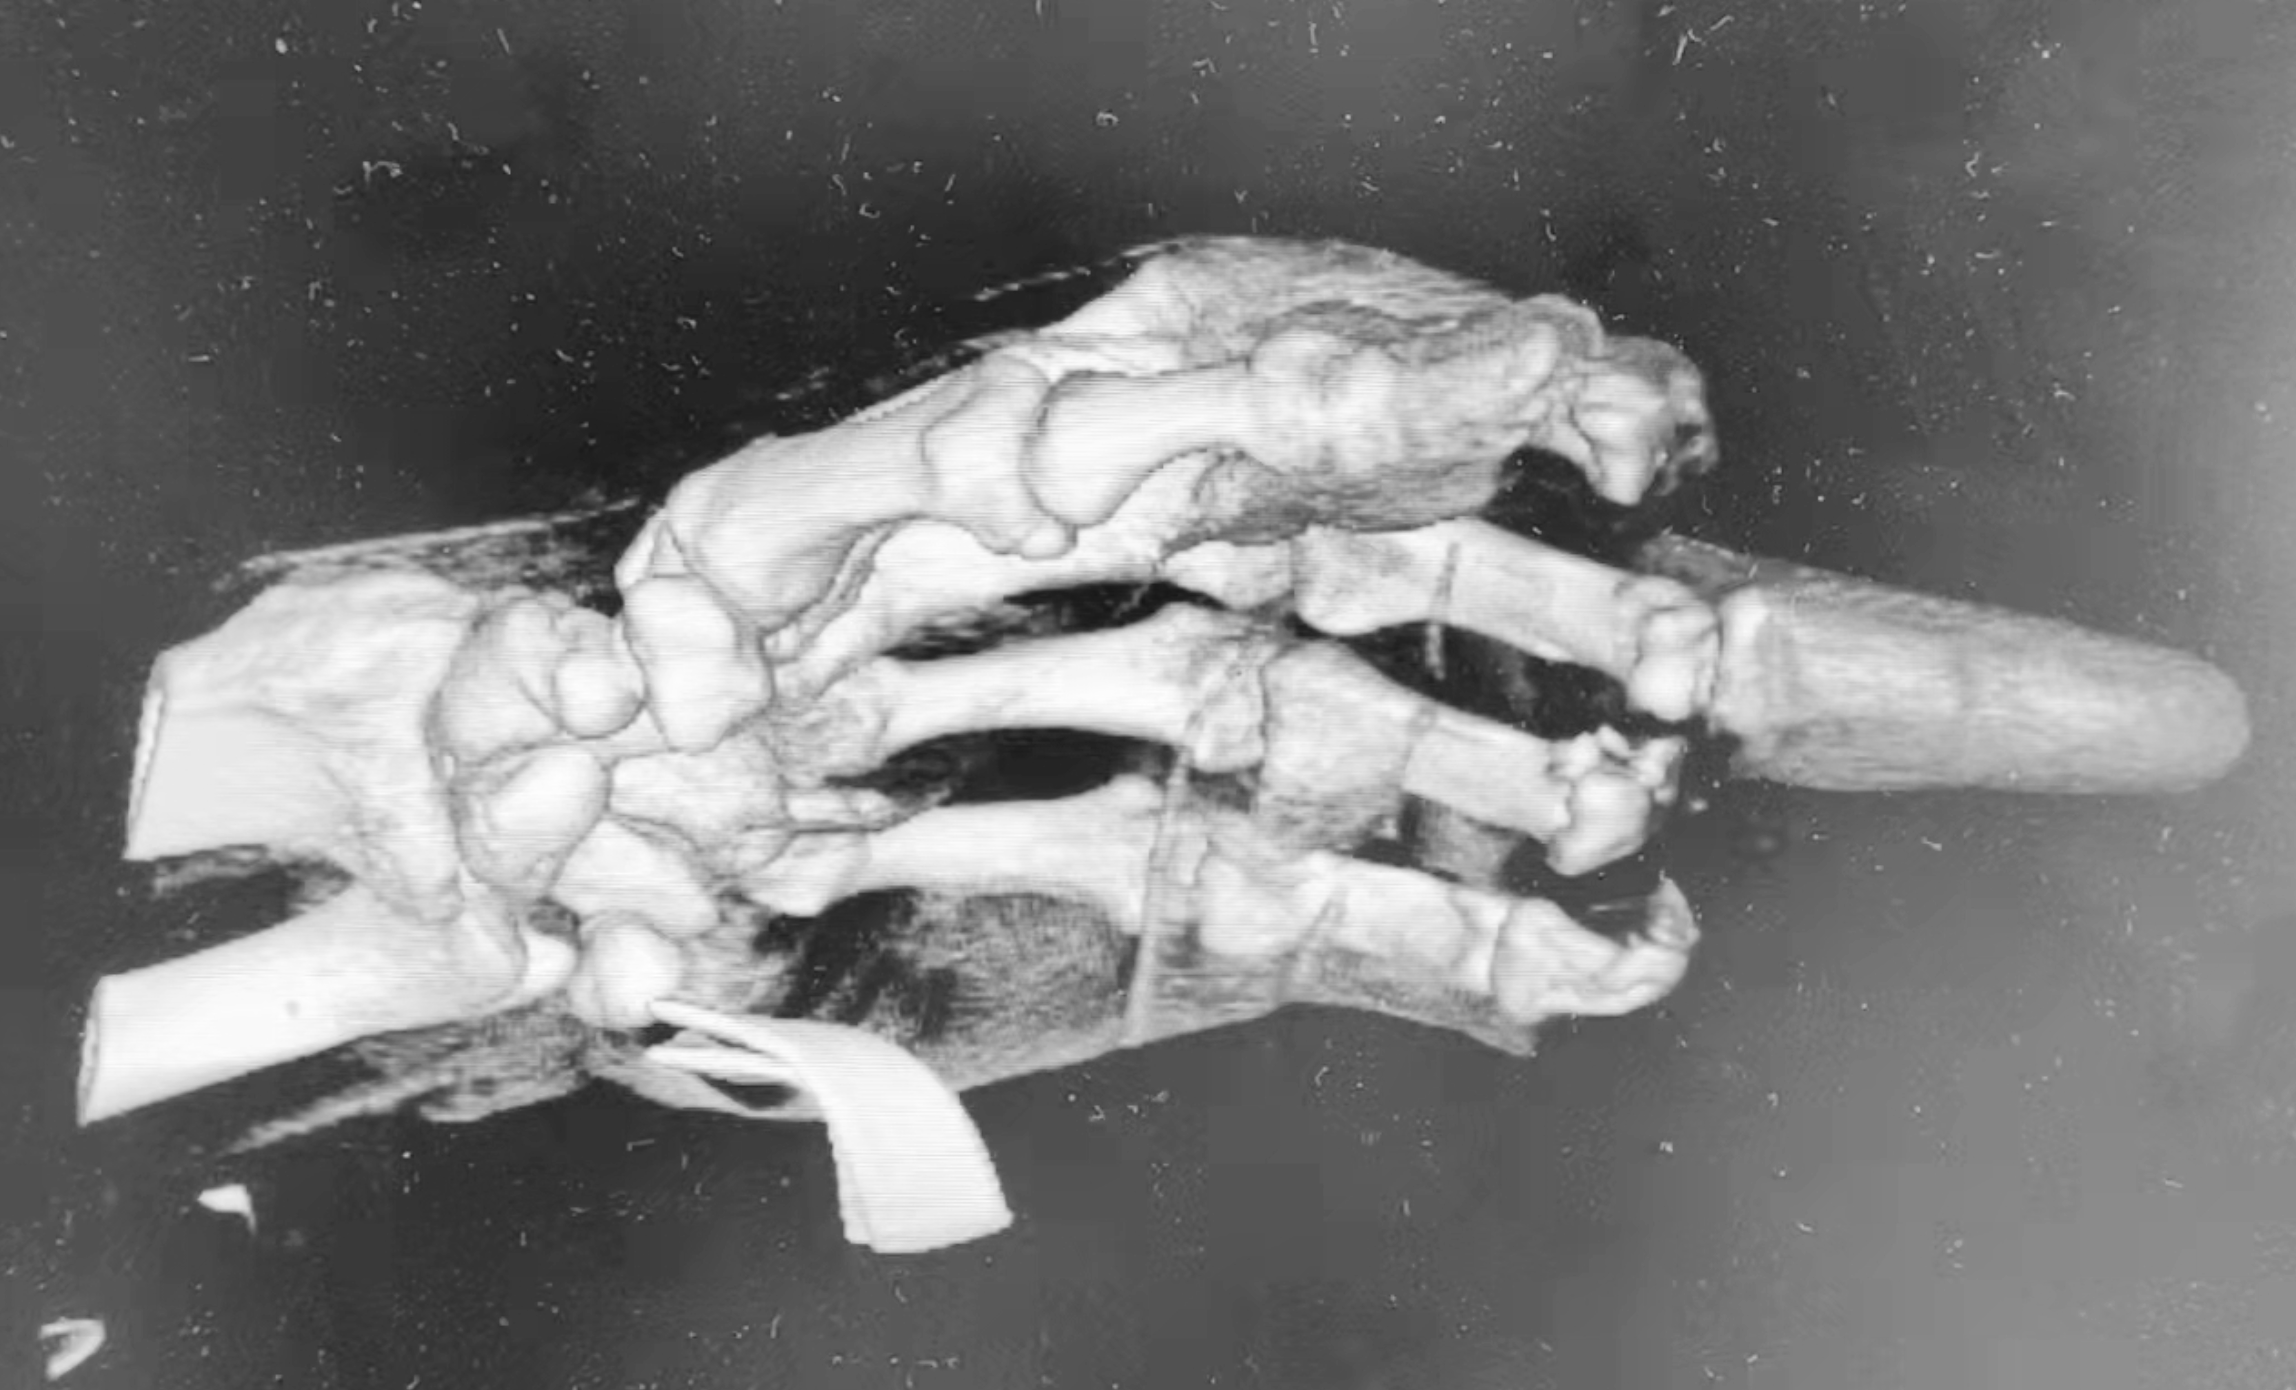

今年2月中旬的一天,晚上11时,老赵冲进了广东省第二人民医院(以下简称“省二医”)急诊科。他的左手用绷带包扎着,右手则拿着三根断指。第二天早上8点,老赵被推出广东省第二人民医院手术室。经过医护人员7小时通宵奋战手术,接指手术非常成功,15条血管、7条神经、7条肌腱接通,基本恢复了手指的外形。

在等待核酸结果以及手术前的准备,3小时后,开始手术。历经7个多小时,手术团队共给老赵的手指吻合了15条血管、7条神经、7条肌腱。